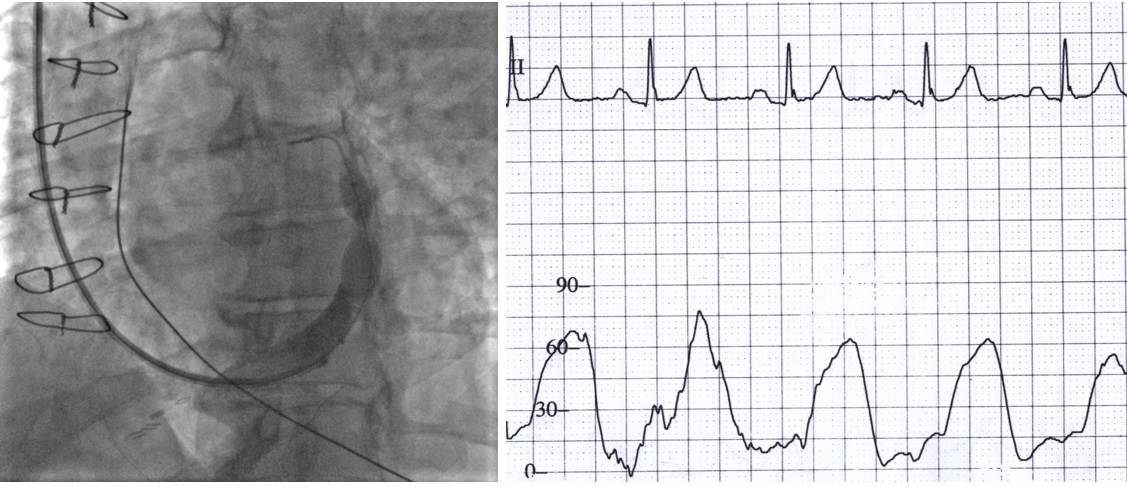

Patients were randomized to either CSR implantation or a sham procedure. The CSR implantation technique is already described elsewhere [7, 8]. Following the right internal jugular vein puncture, the right atrial pressure was measured, followed by cannulation and venography of the coronary sinus. CSR was implanted in the distal coronary sinus with special care not to obstruct any greater tributary and with 10% oversizing to ensure stability. During CSR balloon inflation, occlusion pressure of the coronary sinus proximal to the CSR was measured. After final CSR positioning in the distal coronary sinus, the CSR balloon catheter was connected to the pressure transducer via incompressible plastic tubing. The pressure transducer was positioned at the level of the phlebostatic axis, and the reference point was set to the atmospheric pressure. During the inflation of the CSR balloon, the pressure waveform was recorded. The occlusion pressure was determined as a peak pressure recorded during systole (Fig. 1). Final venography confirmed the appropriate position of the device. A sham procedure was performed by the same experienced operator and in the same catheterization laboratory. Cannulation of the right internal jugular vein was followed by right atrial pressure measurement. The time of the procedure was similar to the CSR implantation. Both procedures were performed in hearing isolation. All medical personnel, apart from those performing the procedure, were blinded to the patient allocation.

Fig. 1.Coronary sinus venography and occlusion pressure measurement. Left: Venography during coronary sinus reducer (CSR) implantation, showing the final position of the CSR in the distal coronary sinus. The CSR catheter balloon is still inflated. Right: Pressure tracing in the proximal coronary sinus during the balloon inflation. Systolic pressure was measured during this phase of the procedure to reduce heterogeneity associated with an extensive network of Thebesian veins.